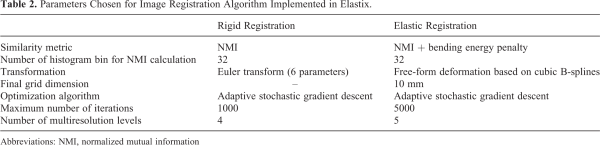

Elastix Software

The deformable transformation between MRI_1 and MRI_2 was estimated using the DIR method implemented in the open-source software Elastix. The chosen registration method is similar to the one implemented in MIM and consists of a rigid realignment followed by the classical FFD based on B-splines, with the parameters optimization available in the Elastix implementation. In particular, the following setup was optimized for a monomodal MRI registration—normalized MI was chosen as the similarity metric, the adaptive stochastic gradient descent as the adopted optimization algorithm, and the stopping criterion was the maximum number of iterations, which were chosen to be sufficiently high to guarantee registration convergence. The complete set of parameters is reported in Table 2.